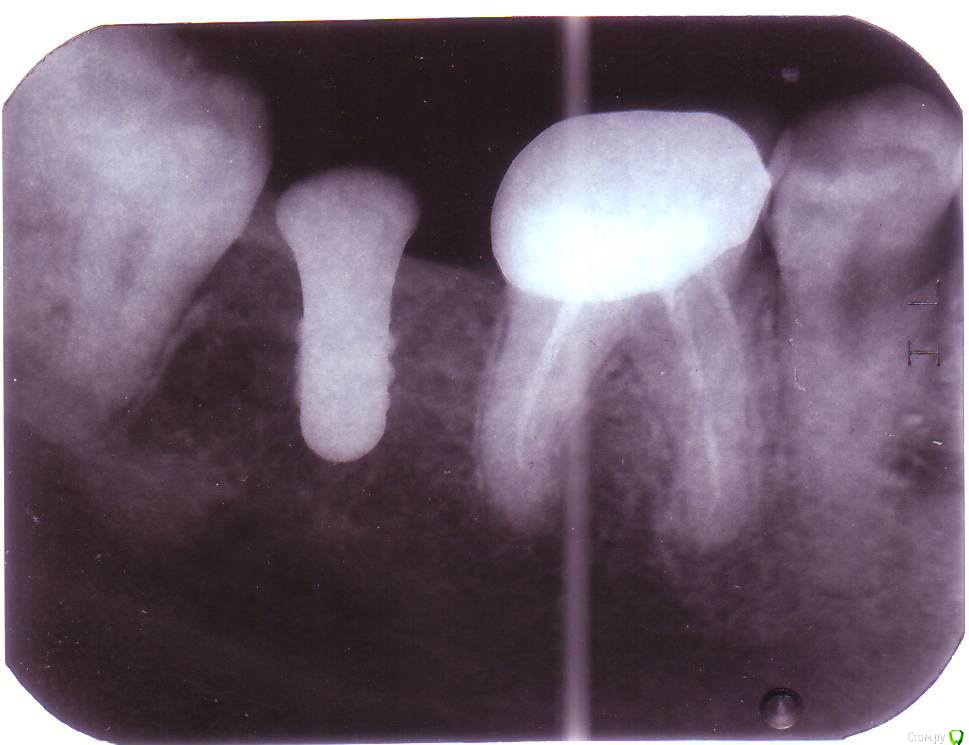

маринаВН Опубликовано 30 января, 2018 Поделиться Опубликовано 30 января, 2018 Добрый день уважаемые врачи. Очень надеюсь на вашу консультацию.3 года назад мне удалили зуб, спустя год я поставила имплант и почти сразу забеременела. Беременность была сложной, поэтому вопрос с зубами я отложила, к сожалению мне никто не сказал, что необходимо поставить хотя бы временную коронку на имплант.После установки импланта прошло уже 2 года, пожалуйста, посмотрите снимок и подскажите, возможно ли что то сделать сейчас? Ссылка на комментарий

dok1 Опубликовано 30 января, 2018 Поделиться Опубликовано 30 января, 2018 Сходите на очный осмотр. Больше толку будет. По снимку вроде неплохо. Ссылка на комментарий

маринаВН Опубликовано 30 января, 2018 Автор Поделиться Опубликовано 30 января, 2018 на очном осмотре была, но не в той клинике где ставили. В одном месте сказали, что можно ставить коронку, а в другом что "имплант наклонился, расстояние между зубом и имплантом маленькое, десна опустилась" записала как поняла - как то не уверенно сказали, что можно нарастить ткани. В общем вопросов оставили больше, чем ответов. Ссылка на комментарий

dok1 Опубликовано 31 января, 2018 Поделиться Опубликовано 31 января, 2018 Наклон импланта не самый удобный. Но визуальный осмотр более информативен. Сходите ещё в клиники сторонние. Послушайте ещё мнения. Ссылка на комментарий

маринаВН Опубликовано 5 февраля, 2018 Автор Поделиться Опубликовано 5 февраля, 2018 Уважаемые врачи, подниму тему.Была еще в одной клинике, остановилась на данном докторе, потому что у него единственного есть аппарат для панорамного рентгена и сносный английский ( живу в ЮВА).По поводу импланта мне сказали, что возможно поставить коронку без наращивания десны и удаления 8ки. Пожалуйста, посмотрите снимок и прокомментируйте.также выяснилось что у меня киста на 6 зубе внизу и недозапломбированы каналы + отвалился кусок зуба - эти каналы я уже раза 3 перепломбировала в разных местах, зуб леченый перелеченный - сказали удалять однозначно. удалили. Там же лет 10 назад мне была удалена 5ка. место это давно занято другими зубами.На верхних 2-3 доктор показал мне белые пятна , сказал, что это начальная стадия кариеса.В связи с тем, что на верхнем зубе у меня уже стоит огромная пломба, ситуация с передними зубами тоже ужасная. Я так понимаю, что остановить процесс образования там кариеса не получится. Возможны ли в будущем виниры , коронки?Мне всего 30 лет. Ощущение, что ситуация катастрофическая и со здоровьем и с эстетикой передних зубов.Извините, за длинное сообщение.Очень надеюсь на Вашу консультацию, к сожалению найти клинику здесь где будут грамотная команда врачей не возможно. я даже не знаю, с чего мне начинать лечение, очень ругаю себя за то что так запустила зубы и хочу сейчас все сделать правильно насколько это возможно. Ссылка на комментарий